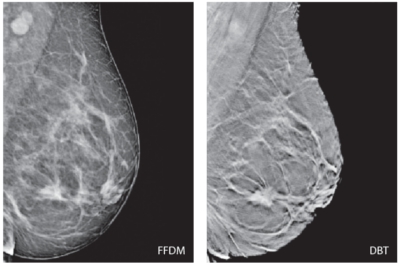

Tehnologia DBT oferă o calitate a imaginii superioară şi implicit informaţie clinică suplimentară prin comparaţie cu mamografia digitală (FFDM**), considerată deja clasică.

Mai mult, un studiu recent desfăşurat în clinica Ospedale Bellaria, a pus în evidenţă faptul că, pentru efectuarea mamografiilor în sistem DBT, este necesară o doză de radiaţii cel mult egală cu doza necesară pentru examinarea FFDM standard (două incidente/sân), iar forţa de compresie în sistem DBT este cel mult egală cu forţa de compresie în sistem FFDM standard.